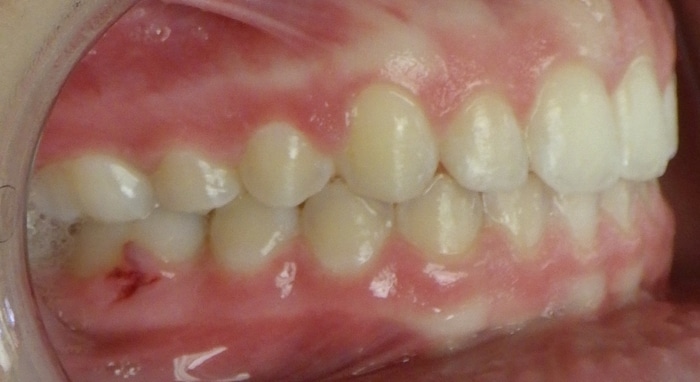

When Marlea presented to us she had a Class II bite with 100% overbite and a 5mm overjet. She also had upper spacing and lower crowding. Marlea’s treatment included metal braces with headgear. With her determination we were able to achieve a Class I bite as well as a perfect overbite and overjet! This is the perfect example of exemplary headgear wear and what a difference it makes in the final outcome of treatment.